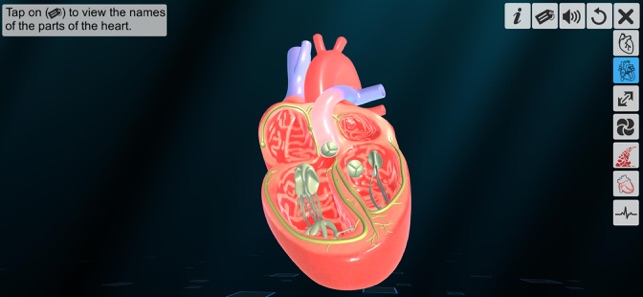

2. Half heart introduction.

‘Heart - An incredible pump’ app explains the external and internal structure of human heart through the simulation 3D model to improve the comprehension of the topic. The user can interact with the 3D model by tapping the model and getting acquainted with the particular part of the human heart. Tapping the model displays the name of the part and also the simulation module is appropriately supported with in depth information about each external and internal structure part.